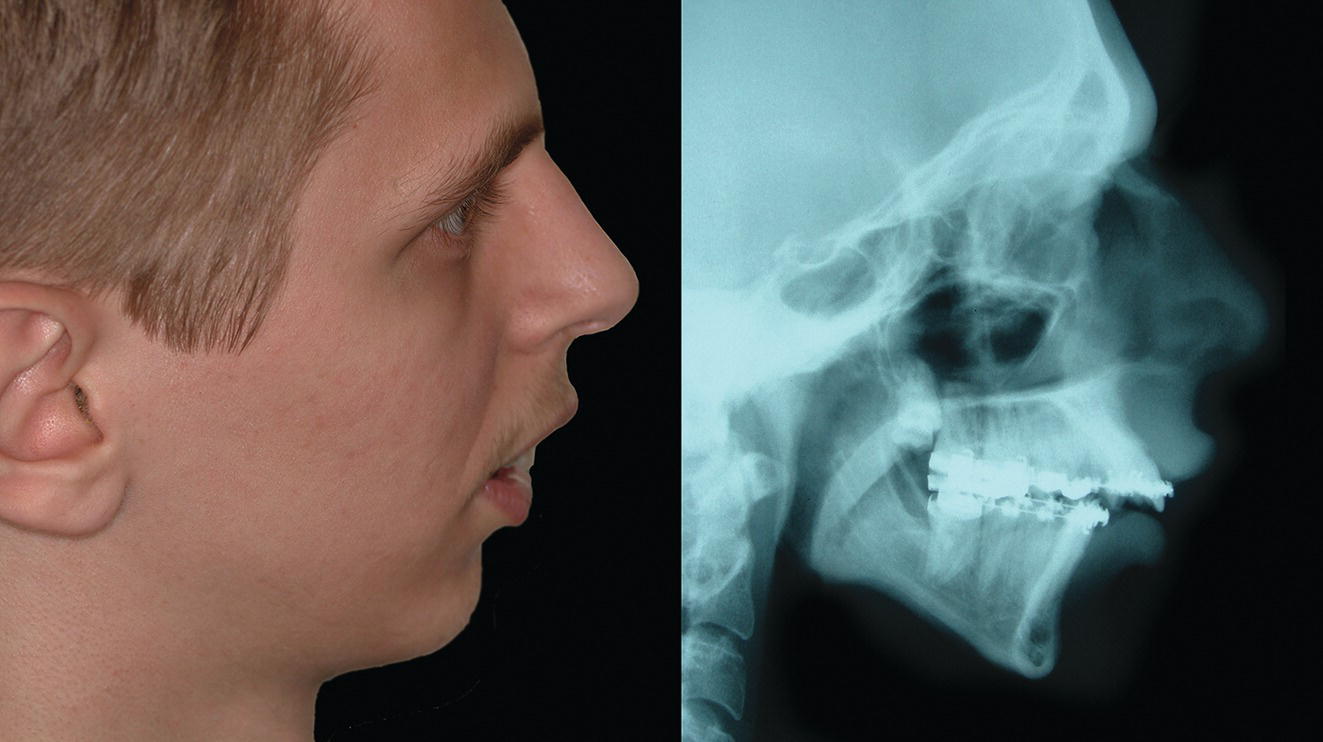

See ‘terminology’ section in Chapter 16. The mandible, the bone of the lower jaw, is one of the most important bones in the craniofacial complex; its anatomy and structural relationships are thus highly significant (Figure 19.1). For descriptive purposes, the mandible may be said to be comprised of a number of subunits: the two main parts are the ramus, which is for articulation and the insertion of jaw‐moving muscles, and the body (corpus), which carries the dentition (Figure 19.2). The body is horseshoe‐shaped when viewed from above, and the two vertical rami project upwards one from each posterior end of the body. The posterior border of the ramus projects upwards as the condylar process, which consists of a neck, expanding into a condylar head or condyle. The body of the mandible projects up around the teeth as alveolar bone, which forms the walls of the tooth sockets. After loss of a tooth the living alveolar bone atrophies. Extensive tooth loss may thereby lead to a reduction in lower anterior face height due to loss of the dentoalveolar process (Figure 19.3). The inferior border of the mandible provides the demarcation between the lower face and neck. The anterior extremity of the mandibular body is the highly variable prominence of the mandibular or mental symphysis (bony chin). Typical morphology: The morphology of the mandible (excluding the bony chin) is relatively consistent, depending on the basic type of dentofacial deformity with which a patient may present, e.g. ‘Class II’, ‘Class III’, ‘short face’ or ‘tall face’. Conversely, the morphology of the bony chin is highly variable and will be described in detail in Chapter 20. Gonial angle (Ar‐Go‐Me): This is a measure of the angle formed between the slope of the posterior border of the mandibular ramus and the mandibular plane. It helps to describe the morphology of the mandible, in particular the relationship between the ramus and the body (Figure 19.4). It is highly correlated with the mandibular plane angle. An increased gonial angle is associated with posterior mandibular growth rotation, and a reduced gonial angle is associated with anterior mandibular growth rotation. In order to determine the relative contribution of the ramus and body of the mandible to mandibular morphology, the gonial angle may be divided into two parts, an upper and lower component, by drawing a facial depth line (nasion‐gonion). The upper component of the gonial angle (50° ± 2°) identifies the inclination of the ramus and the lower component identifies the inclination of the body of the mandible (Figure 19.5).3 Figure 19.1 (A) Oblique right lateral view. (B) Superior view. (C) Oblique left posterior view. Figure 19.2 Mandibular subunits: Figure 19.3 Extensive tooth loss results in resorption of the alveolar process and thereby a reduction in the lower anterior face height; the mandible will rotate anteriorly bringing the chin characteristically closer to the nose. (Head of an Old Man, c. 1487–90, Leonardo da Vinci, Codex Trivulzianus, Sforza Castle, Milan.) Figure 19.4 (A) Reduced, acute gonial angle. (B) Increased, obtuse gonial angle. Figure 19.5 The gonial angle may be divided into an upper and lower component in order to determine the relative contribution of the ramus and body inclination to mandibular morphology. Mandibular growth rotations: Growth rotations of the mandible occur when there is a discrepancy in the amount of anterior and posterior lower facial heights. It is important to bear in mind that the amount of rotation is masked to some extent by periosteal remodelling and dentoalveolar adaptation. Forward (anterior) rotation of the mandible, in the direction of mouth closing, is due to increased posterior vertical facial growth relative to anterior vertical facial growth (Figure 19.6A). Backward (posterior) rotation of the mandible, in the direction of mouth opening, is due to reduced posterior vertical facial growth relative to anterior vertical facial growth (Figure 19.6B). Björk4 described seven structural signs found on a lateral cephalometric radiograph, which may provide an indication to the pattern of mandibular growth (Table 19.1 and Figure 19.7). Inferior border of the mandibular body: The lower border of the mandible should be well‐defined, providing distinct separation of the lower face from the neck. This region will be relatively unattractive in the absence of such demarcation between the lower face and neck, which may be due to skeletal and/or soft tissue factors (Figure 19.8): Figure 19.6 (A) Forward (anterior, anticlockwise) rotation of the mandible, in the direction of mouth closing, is due to increased posterior vertical facial growth relative to anterior vertical facial growth. (B) Backward (posterior, clockwise) rotation of the mandible, in the direction of mouth opening, is due to reduced posterior vertical facial growth relative to anterior vertical facial growth. Table 19.1 Björk’s seven structural signs indicating the pattern of mandibular growth rotation For the numbers refer to Figure 19.7. A thorough clinical evaluation of this region is required, involving clinical inspection and palpation. The lateral cephalometric radiograph, orthopantomograph (OPT) and where necessary three‐dimensional reconstruction of the mandible permits more accurate analysis of the inferior mandibular border. When skeletal and soft tissue factors coexist, surgical correction to redefine the natural demarcation in this region may involve augmentation of the lower mandibular border and gonial angles in conjunction with rhytidectomy. Figure 19.7 Björk’s seven structural signs, which may be used to indicate the pattern of mandibular growth (for an explanation of the numbers, refer to Table 19.1). Figure 19.8 Indistinct inferior border of the mandible. Mandibular micrognathia (a small mandible) may have reasonable proportionality between the ramus and body. Although hypoplasia of the mandible may affect the ramus, body or both, syndromic mandibular deficiency is often due to a short mandibular ramus. The surgical technique of distraction osteogenesis may be used to differentially lengthen the ramus and/or the body of the mandible. The craniofacial dimensions of patients with craniofacial syndromes in particular may not fit into normal ranges of variability. Therefore, the use of proportional analysis rather than comparison with population ‘norms’ is a useful method of evaluating the specific area (ramus or body), direction and extent of lengthening that may be required. The characteristic feature of sagittal mandibular deficiency, and the most common complaint from the ‘Class II’ patient, is the retruded position of the chin relative to the rest of the face in profile view. It is important to distinguish true skeletal mandibular deficiency from relative mandibular deficiency. True sagittal mandibular deficiency may be due to: Relative mandibular deficiency may be due to: Table 19.2 Normal mandibular dimensions (white Caucasian adults) Refer to Figure 19.9. Figure 19.9 Mandibular dimensions (for normative values see Table 19.2). The aetiology of mandibular deficiency may result from a combination of relative and true mandibular deficiency. The diagnostic features of sagittal mandibular deficiency depend to a great extent on the lower anterior facial height (LAFH). In patients with sagittal mandibular deficiency and a normal or reduced LAFH, the diagnostic features are (Figure 19.10): Figure 19.10 Sagittal mandibular deficiency with a reduced lower anterior facial height. Figure 19.11 Sagittal mandibular deficiency with an increased lower anterior facial height. In patients with sagittal mandibular deficiency and an increased LAFH, the diagnostic features are (Figure 19.11): The aetiology of Class III jaw deformity, in particular mandibular excess, has a very strong genetic basis.7 The familial tendency of Class III deformity may be frequently observed in members of the same family. A famous example is of the Hapsburg dynasty, one of the German royal families. Over 23 generations, portrait painters have captured images of the Hapsburgs, and they all exhibit the same mandibular prognathism and protrusive lower lip, often termed the ‘Hapsburg jaw’ (Figure 19.12). In addition, evidence from twin studies has suggested the strongest genetic predisposition for Class III malocclusion, with concordance in identical twins six times higher than in non‐identical twins for mandibular prognathism.8 Although there is a strong familial occurrence, there seems to be no association with sex, with different modes of transmission in different families or populations.9 Edward Angle, described as the father of modern orthodontics, recognized early in the twentieth century that severe mandibular excess could only be corrected through a combination of orthodontics and mandibular surgery (Figure 19.13).10 The characteristic feature of mandibular excess, and the most common complaint from the ‘Class III’ patient, is the prominence of the chin and lower lip relative to the rest of the face in profile view (Figure 19.14). It is important to distinguish true skeletal mandibular excess from relative mandibular excess. Figure 19.12 The prominent ‘Hapsburg jaw’ and protrusive lower lip of the Hapsburg dynasty is evident in the portraits of (A) Charles V, Holy Roman Emperor (1500–58) and (B) Charles II of Spain (1661–1700). Figure 19.13 The ‘chin retractor’ of Edward Angle was a predecessor to the chin cup (chin cap) used by orthodontist in the attempt to correct mandibular excess in young patients by restraining mandibular condylar growth; Angle later recognized the limitations of such appliances. True sagittal skeletal mandibular excess may be due to: True skeletal mandibular excess must be distinguished from relative (apparent) mandibular excess. Conditions in which the mandible appears excessively prominent are: Figure 19.14 The characteristic feature of mandibular excess is the prominence of the chin and lower lip relative to the rest of the face in profile view. The two contrasting heads demonstrate an attractive profile (left panel) and a ‘Class III’ profile with mandibular excess and protrusive lower lip (right panel). (Michelangelo, c. 1516–24, The Ashmolean Museum, Oxford.) The aetiology of mandibular excess often results from a combination of relative and true mandibular excess.